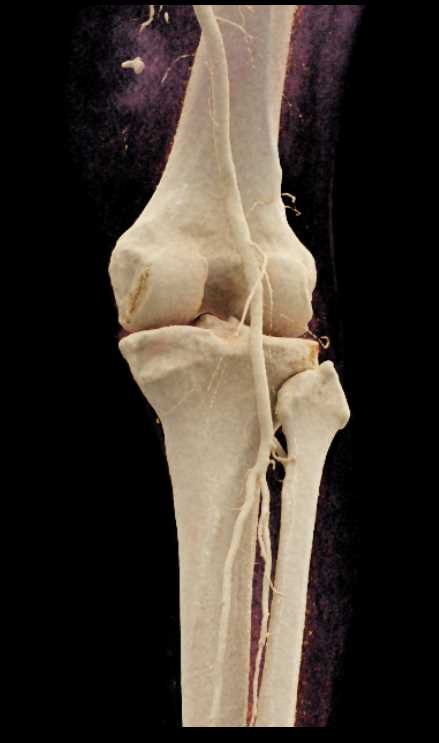

GSW with Bleed Near Knee